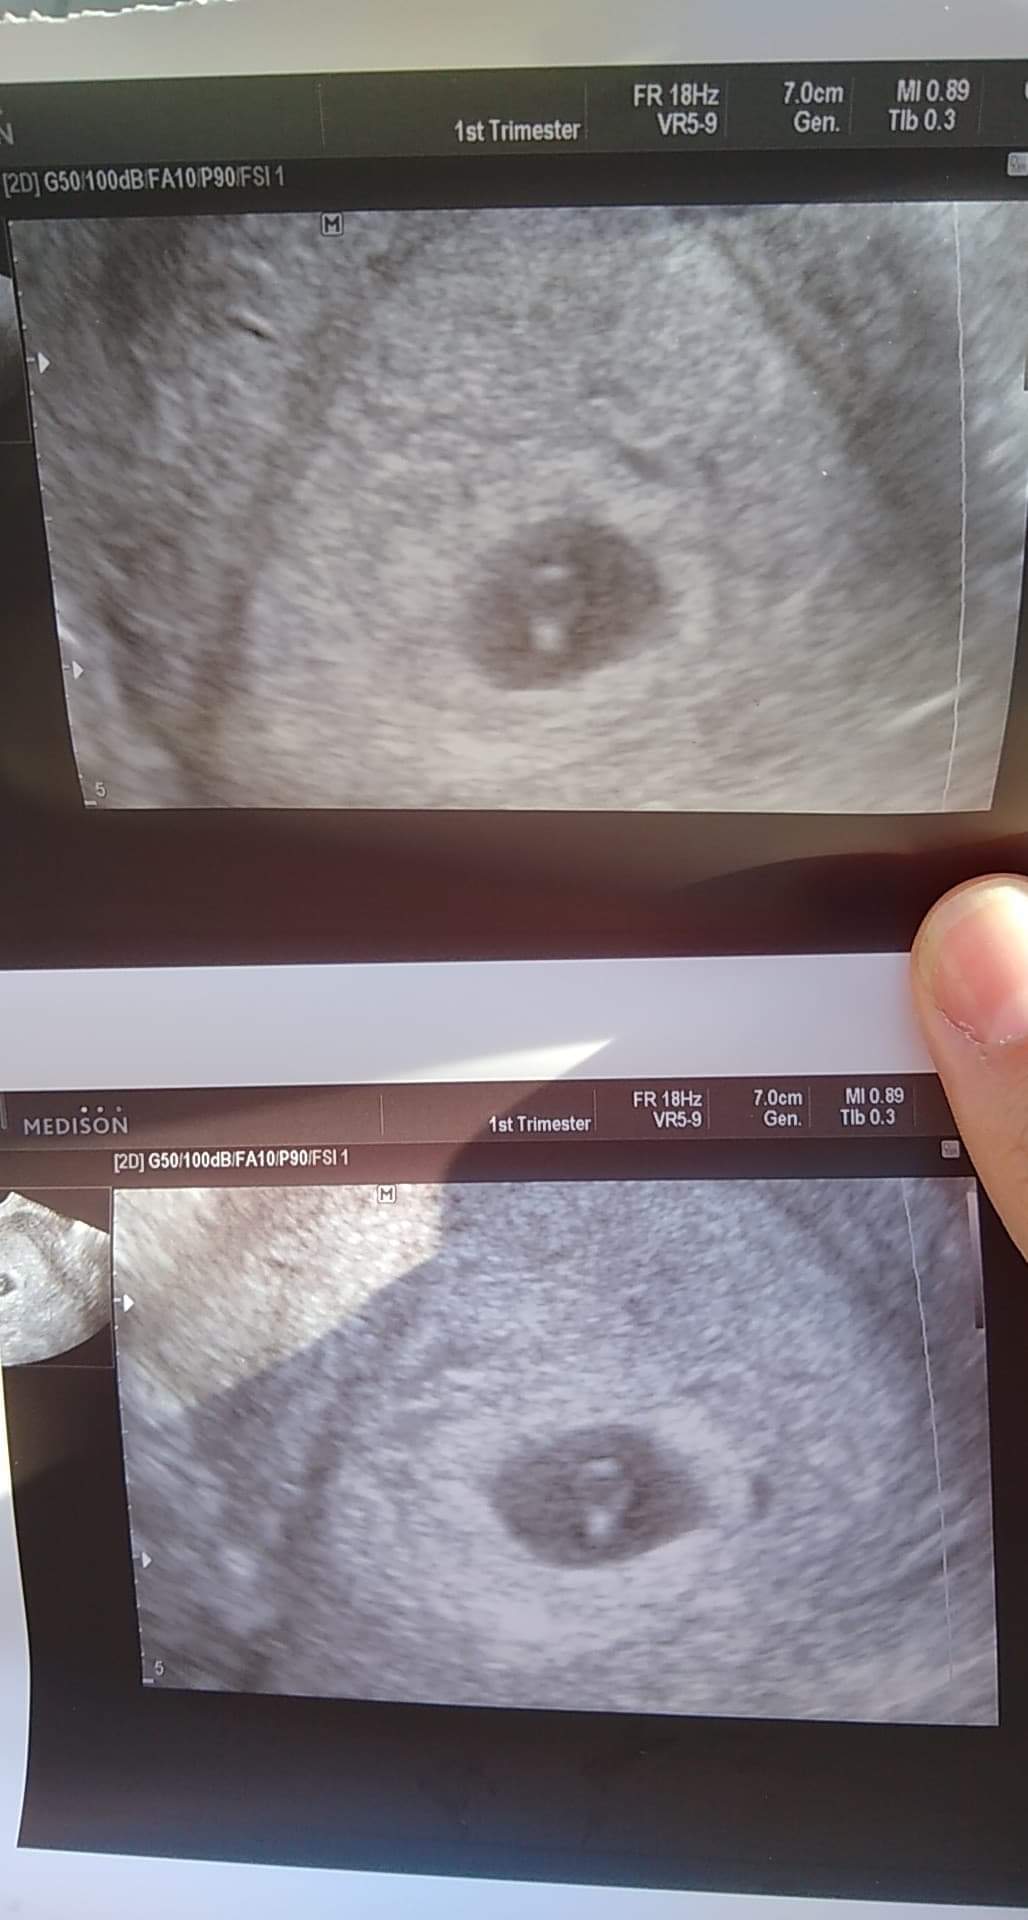

Dziewczyny pewnie myślicie że zwariowałam 🙈🙈🙈ale tak mnie niepokoiło że tydzień temu nie było widać zarodka a tu się naczytałam i nakręciłam że może mam pusty pęcherzyk i się umówiłam na dziś do lekarza. Serduszka jeszcze nie widać ale zarodek już tak :) dziś według om 6+2 received_2651453228517673.jpeg

Ja zawsze pierwsze dopochwowe... nawet na 3d w 13 tyg musiała zmienić na takie bo jednak przez powłoki jest gorzej widoczna tak wczesna ciąża